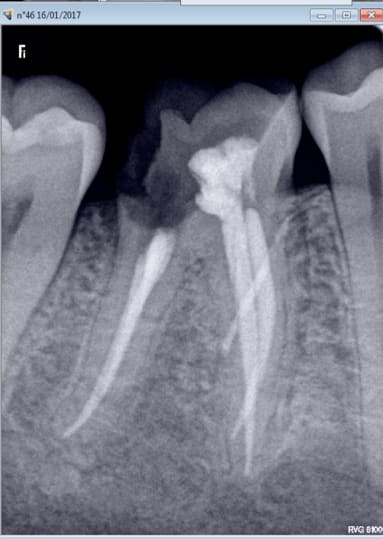

Tiens casa quand tu soignes la dent causale tu ne les revois plus........ non plus.

Enfin des fois si. 2006........2017. Et pas pour une visite de controle. -) -)

Je pense qu'il y a une image apicale sur 16 car je n'avais pas traité le MV2 à l'époque. Heureusement que je n'ai pas fait de couronne hein ? -) -))))

C'est la 15 qui a motivé la consult. Bizarre. -))))

Je vais commencer par 27....... une fois le devis signé ! -)))))))

Ah oui radios 8 secteurs. -))))

AH ! oui il a tardé en plus ( endo en avril 2016) ca n'arrange pas les choses-)))

PS: putain , j'avais pas vu les radio ,ç est bo que ç en devient enervant :-)

Oui l'année dernière. je me demandais si c'était pas l'aiguille du quick sleeper qui avait traversé la racine. -)

Avant thermocompaction et après thermocompaction. Et merde. -)

Mais bon RAS 10 mois après. Si ce n'est qu'elle a perdu de la durée devie car c'était un peu ramollo au niveau du canal distal. J'aurais bien fait le pivot dans un des mésiaux mais j'ai pas osé. -)))